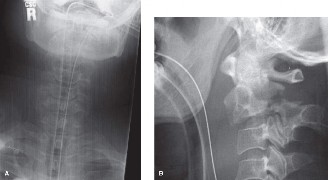

A 32-year-old male competitive weightlifter complains of persistent, deep, aching low back pain that began subtly and gradually worsened over several months. The pain is exacerbated by lumbar extension and resisted hip flexion, and he reports a 'catch' when transitioning from flexion to extension. Physical examination reveals tenderness to palpation over the L5-S1 region and a positive single-leg hyperextension test (Stork test). Neurological examination is unremarkable. Which imaging study would be most appropriate for initial evaluation?

The patient's history (young athlete, extension-related pain, 'catch', tenderness over L5-S1, positive Stork test) is highly suggestive of spondylolysis, particularly a pars interarticularis defect. While MRI can visualize soft tissues well, plain radiographs including oblique views are the initial imaging of choice to diagnose spondylolysis by demonstrating the 'Scottie dog' collar defect in the pars interarticularis. If plain films are inconclusive or further characterization is needed, a CT scan might follow, especially for visualizing bone detail. MRI is excellent for disc and neural structures but less sensitive for early pars defects. A bone scan might be used to assess for active stress reaction in the pars, but radiographs are first-line for structural defects. EMG/NCS are for evaluating nerve impingement and are not indicated here as the neurological exam is unremarkable.